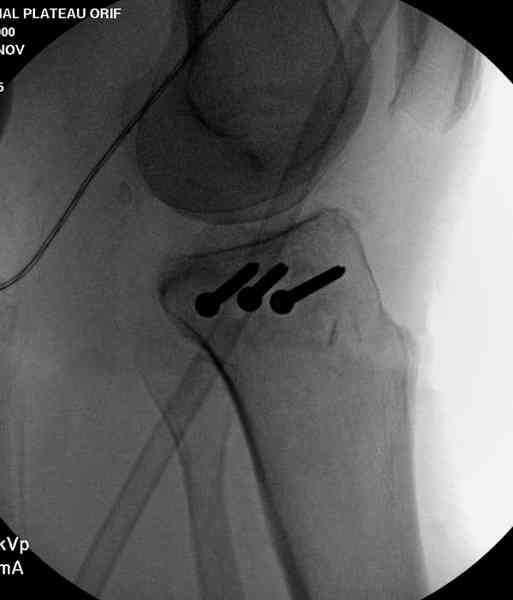

>Вы контролируете положение малоберцового

> нерва?

Нет, малоберцовый внизу, фиксацию проводим на верхнем эпифизе, где твердая кость. Задача состоит

в том, чтобы создать арматуру из нескольких проведенных шурупов на эпифизе.

Медиально, обычно на протовоположной

строне, делается окно в кортикальном слое, кривым забойником под рентгеном поднимается импрессия.